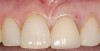

A 59-year-old woman presented with a recent history of trauma to her pre-maxilla, resulting in vertical root fracture of the maxillary left central incisor (Figure 1 and Figure 2). Examination revealed a mobile crown, moderate flat periodontal biotype, gingival margin of the left central incisor 1 mm coronal to that of the adjacent central incisor, central incisor tooth width discrepancy, and a medium smile line. The treatment plan included flapless extraction of the fractured tooth with the potential for simultaneous socket grafting using mineralized bone allograft (MinerOss®, BioHorizons, Inc, Birmingham, AL) and a free gingival graft (Figure 3) harvested from the left palate. Post-extraction examination revealed vertical labial plate loss of 2 mm and class I interproximal height of bone; therefore, all three procedures were performed. Four months postsurgery (Figure 4), a mid-crestal and sulcular incision without release was made to allow for crestal plasty and core biopsy (Figure 5). Histomorphometry revealed 87% vital bone with minimal evidence of residual allograft (Figure 6). This finding was consistent with type II bone density and allowed for non-submerged implant placement. The labial plate was completely regenerated. A provisional crown was placed and contoured to groom the soft tissue for 3 months (Figure 7), followed by final crown fabrication (Figure 8).

Figure 8  Completed crown on the maxillary left central incisor.

Figure 8